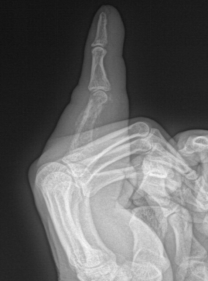

掌骨骨折;指骨骨折;手舟骨骨折

足舟骨骨折;跖骨骨折;楔骨骨折;跟骨骨折

粉碎性骨折;撕脱性骨折;疲劳性骨折